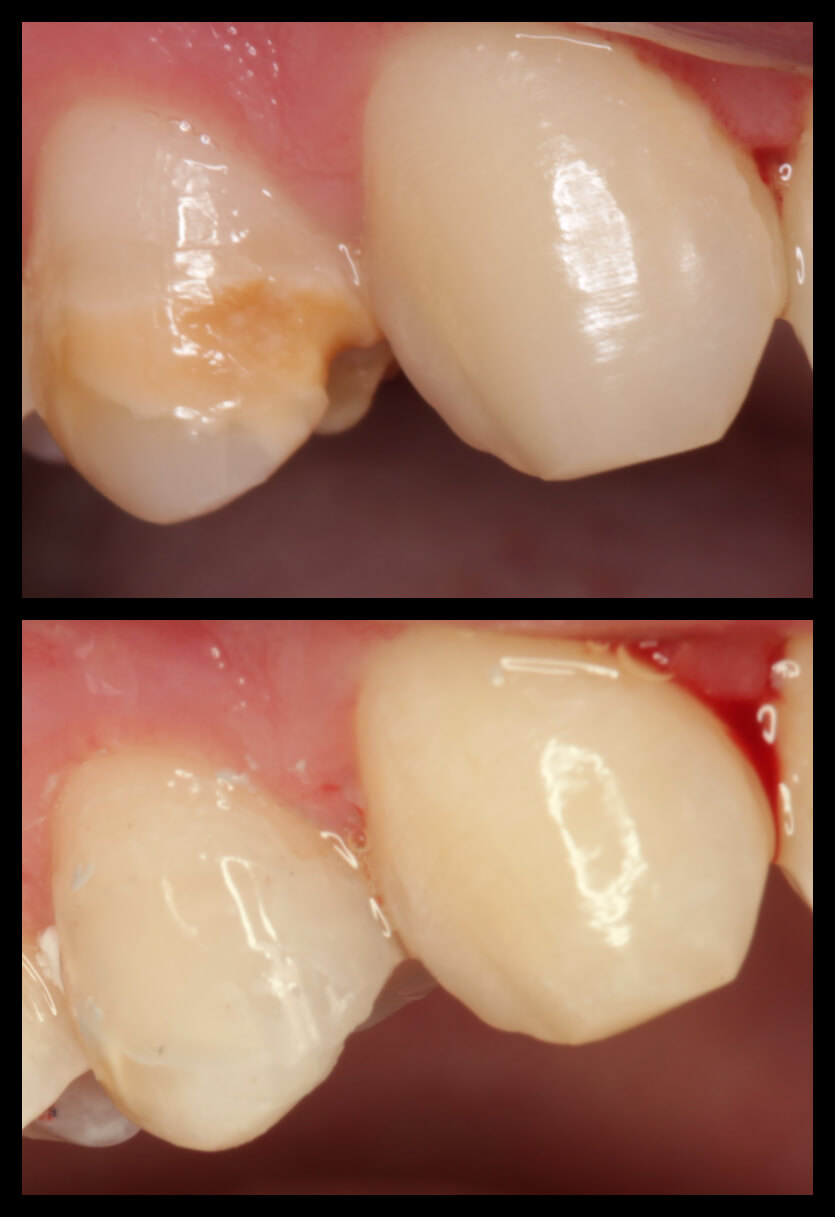

ΠΕΡΙΣΤΑΤΙΚΑ ΜΕ ΤΟΠΟΘΕΤΗΣΗ ΕΝΔΟΟΣΤΙΚΩΝ ΕΜΦΥΤΕΥΜΑΤΩΝ. ΌΠΟΥ ΧΡΕΙΑΣΤΗΚΕ ΠΡΑΓΜΑΤΟΠΟΙΗΘΗΚΕ ΑΝΑΠΛΑΣΗ ΟΣΤΟΥ ΚΑΙ ΟΥΛΙΚΩΝ ΕΛΕΙΜΜΑΤΩΝ ΜΕ ΧΡΗΣΗ ΜΟΣΧΕΥΜΑΤΩΝ ΚΑΙ PRF